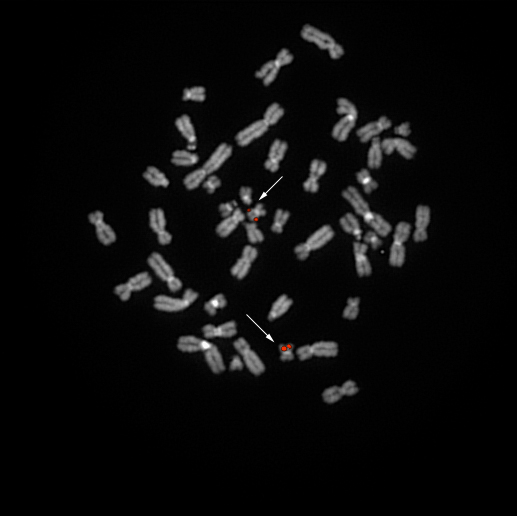

bA702B14